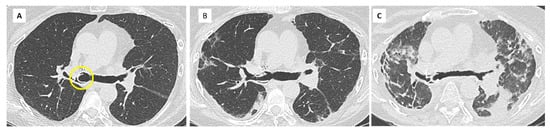

- Dubbeldam, A.; Barthels, C.; Coolen, J.; Verschakelen, J.A.; Verleden, S.E.; Vos, R.; Verleden, G.M.; De Wever, W. Restrictive allograft syndrome after lung transplantation: New radiological insights. Eur. Radiol. 2016, 27, 2810–2817. [Google Scholar] [CrossRef]

- Sato, M.; Hwang, D.M.; Waddell, T.K.; Singer, L.G.; Keshavjee, S. Progression pattern of restrictive allograft syndrome after lung transplantation. J. Heart Lung Transplant. 2013, 32, 23–30. [Google Scholar] [CrossRef]

- Ofek, E.; Sato, M.; Saito, T.; Wagnetz, U.; Roberts, H.C.; Chaparro, C.; Waddell, T.K.; Singer, L.G.; Hutcheon, M.A.; Keshavjee, S.; et al. Restrictive allograft syndrome post lung transplantation is characterized by pleuroparenchymal fibroelastosis. Mod. Pathol. 2013, 26, 350–356. [Google Scholar] [CrossRef]

- Verleden, S.E.; de Jong, P.A.; Ruttens, D.; Vandermeulen, E.; Van Raemdonck, D.E.; Verschakelen, J.; Vanaudenaerde, B.M.; Verleden, G.M.; Vos, R. Functional and computed tomographic evolution and survival of restrictive allograft syndrome after lung transplantation. J. Heart Lung Transplant. 2014, 33, 270–277. [Google Scholar] [CrossRef] [PubMed]

- Glanville, A.R.; Verleden, G.M.; Todd, J.L.; Benden, C.; Calabrese, F.; Gottlieb, J.; Hachem, R.R.; Levine, D.; Meloni, F.; Palmer, S.M.; et al. Chronic lung allograft lung dysfunction: Definition and update of restrictive allograft syndrome. A consensus report from the Pulmonary Council of the ISHLT. J. Heart Lung Transplant. 2019, 38, 483–492. [Google Scholar] [CrossRef]

- Konen, E.; Weisbrod, G.L.; Pakhale, S.; Chung, T.; Paul, N.S.; Hutcheon, M.A. Fibrosis of the Upper Lobes: A Newly Identified Late-Onset Complication After Lung Transplantation? Am. J. Roentgenol. 2003, 181, 1539–1543. [Google Scholar] [CrossRef]